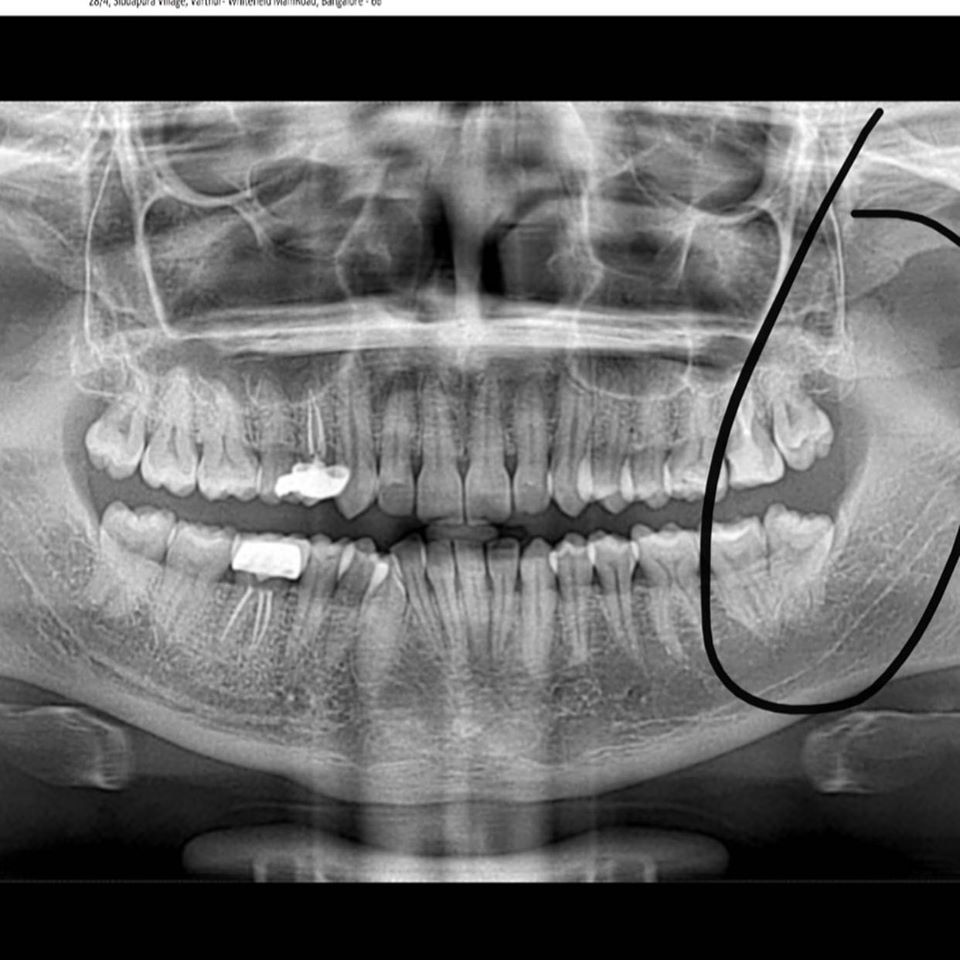

Scaling, Restoration, Esthetic Restoration, Extraction, Root Canal Treatment and Crown, Veneers and Laminates, Bleaching, Orthodontic Treatment, Implants, Periodontal Problems, Child Dental Care, Surgical Procedure, Smile Designing, etc. We are the best dental clinic in Whitefield, the best dental clinic in Brookefield & the best dental clinic in Varthur Road.